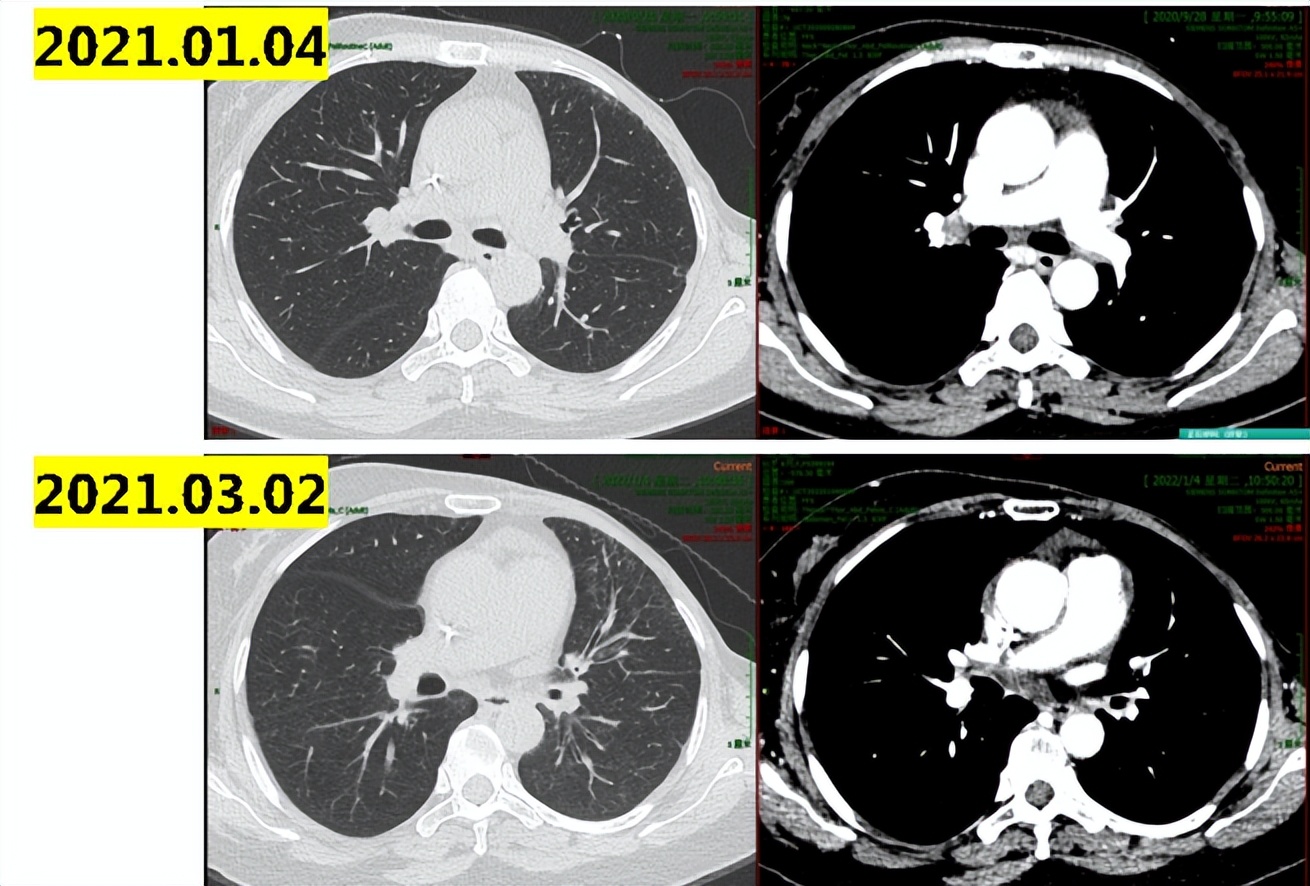

2021.6.10复查肺部ct示:双肺散在实性结节,最大10×8mm,部分病灶较前稍增大;纵隔及肺门淋巴结增大,最大直径13mm(图1-3),考虑病情进展。

图1-3

2021.06-2021.09入组:XZP-3287(吡罗西尼)治疗中国晚期恶性实体瘤受试者的多中心、开放性Ⅰ/Ⅱ期临床研究,2021.09初患者开始出现胸闷气喘,2021.09.17肺部CT示:双肺下叶炎性病变,双肺下叶小叶间隔增厚,考虑间质性病变;双肺散在结节影,部分同前相仿,部分较前新发,考虑转移可能;心包积液,较前增多。示双肺及叶间裂胸膜处多发小结节,较前新发,考虑病情进展(图1-4)。

图1-4

讨论意见:患者CDK4/6*制剂抑**治疗后出现间质性肺炎改变,建议行抗生素+激素治疗。诊断为乳腺癌综合治疗后进展(双肺、纵隔、心包积液),建议行心包积液穿刺引流+沉渣包埋明确病理和分子分型,再决定进一步治疗方案。

心包穿刺引流:查见癌细胞,提示乳腺来源可能性大。ER(-),PR(-),HER2(0),Ki67(LI:20%)。备注:细胞沉渣制成蜡块1个,镜下查见癌细胞数量约300个,所占比例<1%。提示患者已经由HR+转成三阴型乳腺癌。患者给予抗生素、激素治疗后患者症状好转,行长春瑞滨口服周方案化疗5周。

2021.11患者再次出院胸闷气喘,2021.11.05复查肺部CT示:双肺新增斑片影、小叶间隔增厚,考虑间质性炎症或感染性病变,较前新增;左肺下叶支扩伴感染,双肺散在结节影,左肺上叶新增结节,考虑转移可能;少量心包积液(图1-5)。

图1-5

行抗生素激素治疗后患者症状明显缓解,影像学提示间质性改变较前明显改善(图1-6),2021.11.23-2022.04行UTD1化疗6周期,疗效评价PR(图1-7,1-8)。

图1-6

图1-7

图1-8